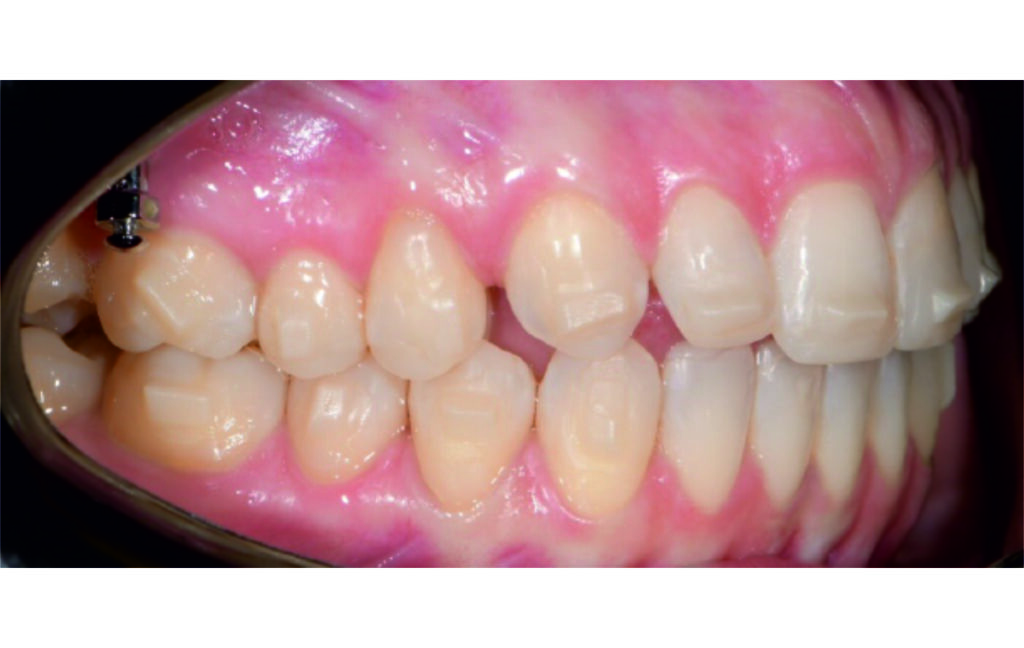

A 1.5 mm deviation of the upper dental midline to the patient’s left was noted, along with a slight mandibular midline shift to the right, likely due to asymmetrical mandibular growth observed in the facial structure. Severe mesial rotations of teeth 16 and 26 were evident in the initial records. As derotation of 16, 26, 17, and 27 progressed up to aligner 16, the premolars in segments I and II moved distally, resulting in a bilateral Class I relationship, as intended in the initial treatment plan.

Derotation of 16 26 allowed Class II correction.

Vertical vector of elastic traction on buttons and IZC helped with the open bite correction.

No sequential distalization for Class II tendency correction was performed due to skeletal anchorage. Lingual attachments were used to improve aligner grip and control tooth movement, as small, angulated lower incisors are difficult to move due to limited anatomy.

An infrazygomatic crest (IZC) screw with force applied between the upper premolars produces a clockwise rotation of the maxillary occlusal plane. This movement aids in closing the anterior open bite and improves upper incisor display. IZC screws with elastics also enable planned intrusion of the upper molars by 1 mm. Because mandibular derotation after upper posterior correction is difficult to predict, anterior distalization and midline correction were performed in the later stages of treatment.